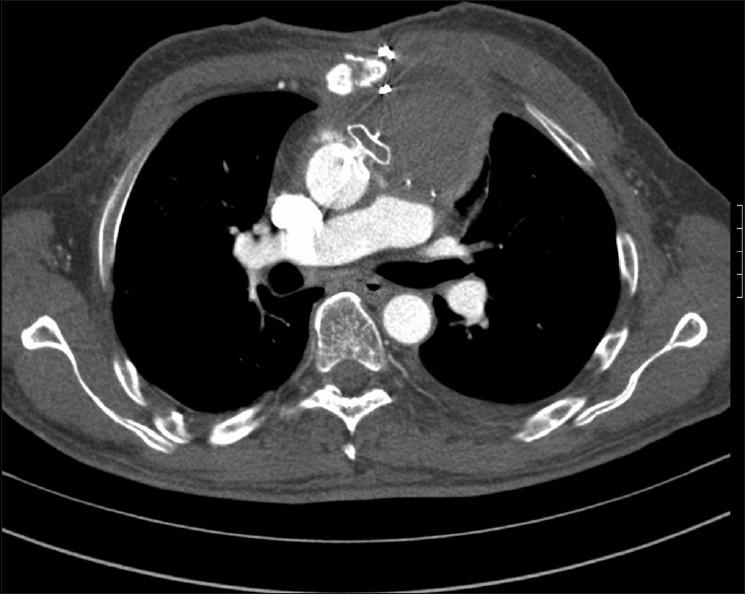

Pseudoaneurysm of ascending aorta is an infrequent but well-recognized and potentially fatal complication after cardiac surgeries. The complication can develop early, delayed or late, and the presentation is also varied. We are presenting here two cases of pseudoaneurysm of ascending aorta following cardiac surgery that were successfully managed by the transcatheter method. The first one occurred following coronary artery bypass surgery and the second one occurred following double-valve replacement surgery. The aortic openings of these aneurysms were occluded with 12 mm and 10 mm atrial septal occluders, respectively, with a good outcome. An immediate postprocedure angiogram showed no residual flow into the sac. Six months of follow-up of both cases also showed excellent results.

升主动脉假性动脉瘤是心脏手术后一种罕见但已被充分认识且可能致命的并发症。该并发症可早期、延迟或晚期发生,表现也各不相同。我们在此呈现两例心脏手术后升主动脉假性动脉瘤病例,均通过经导管方法成功治疗。第一例发生在冠状动脉旁路移植术后,第二例发生在双瓣膜置换术后。这些动脉瘤的主动脉开口分别用12毫米和10毫米的房间隔封堵器封堵,效果良好。术后即刻血管造影显示无血液残留进入瘤腔。两例患者术后6个月的随访结果也都非常理想。